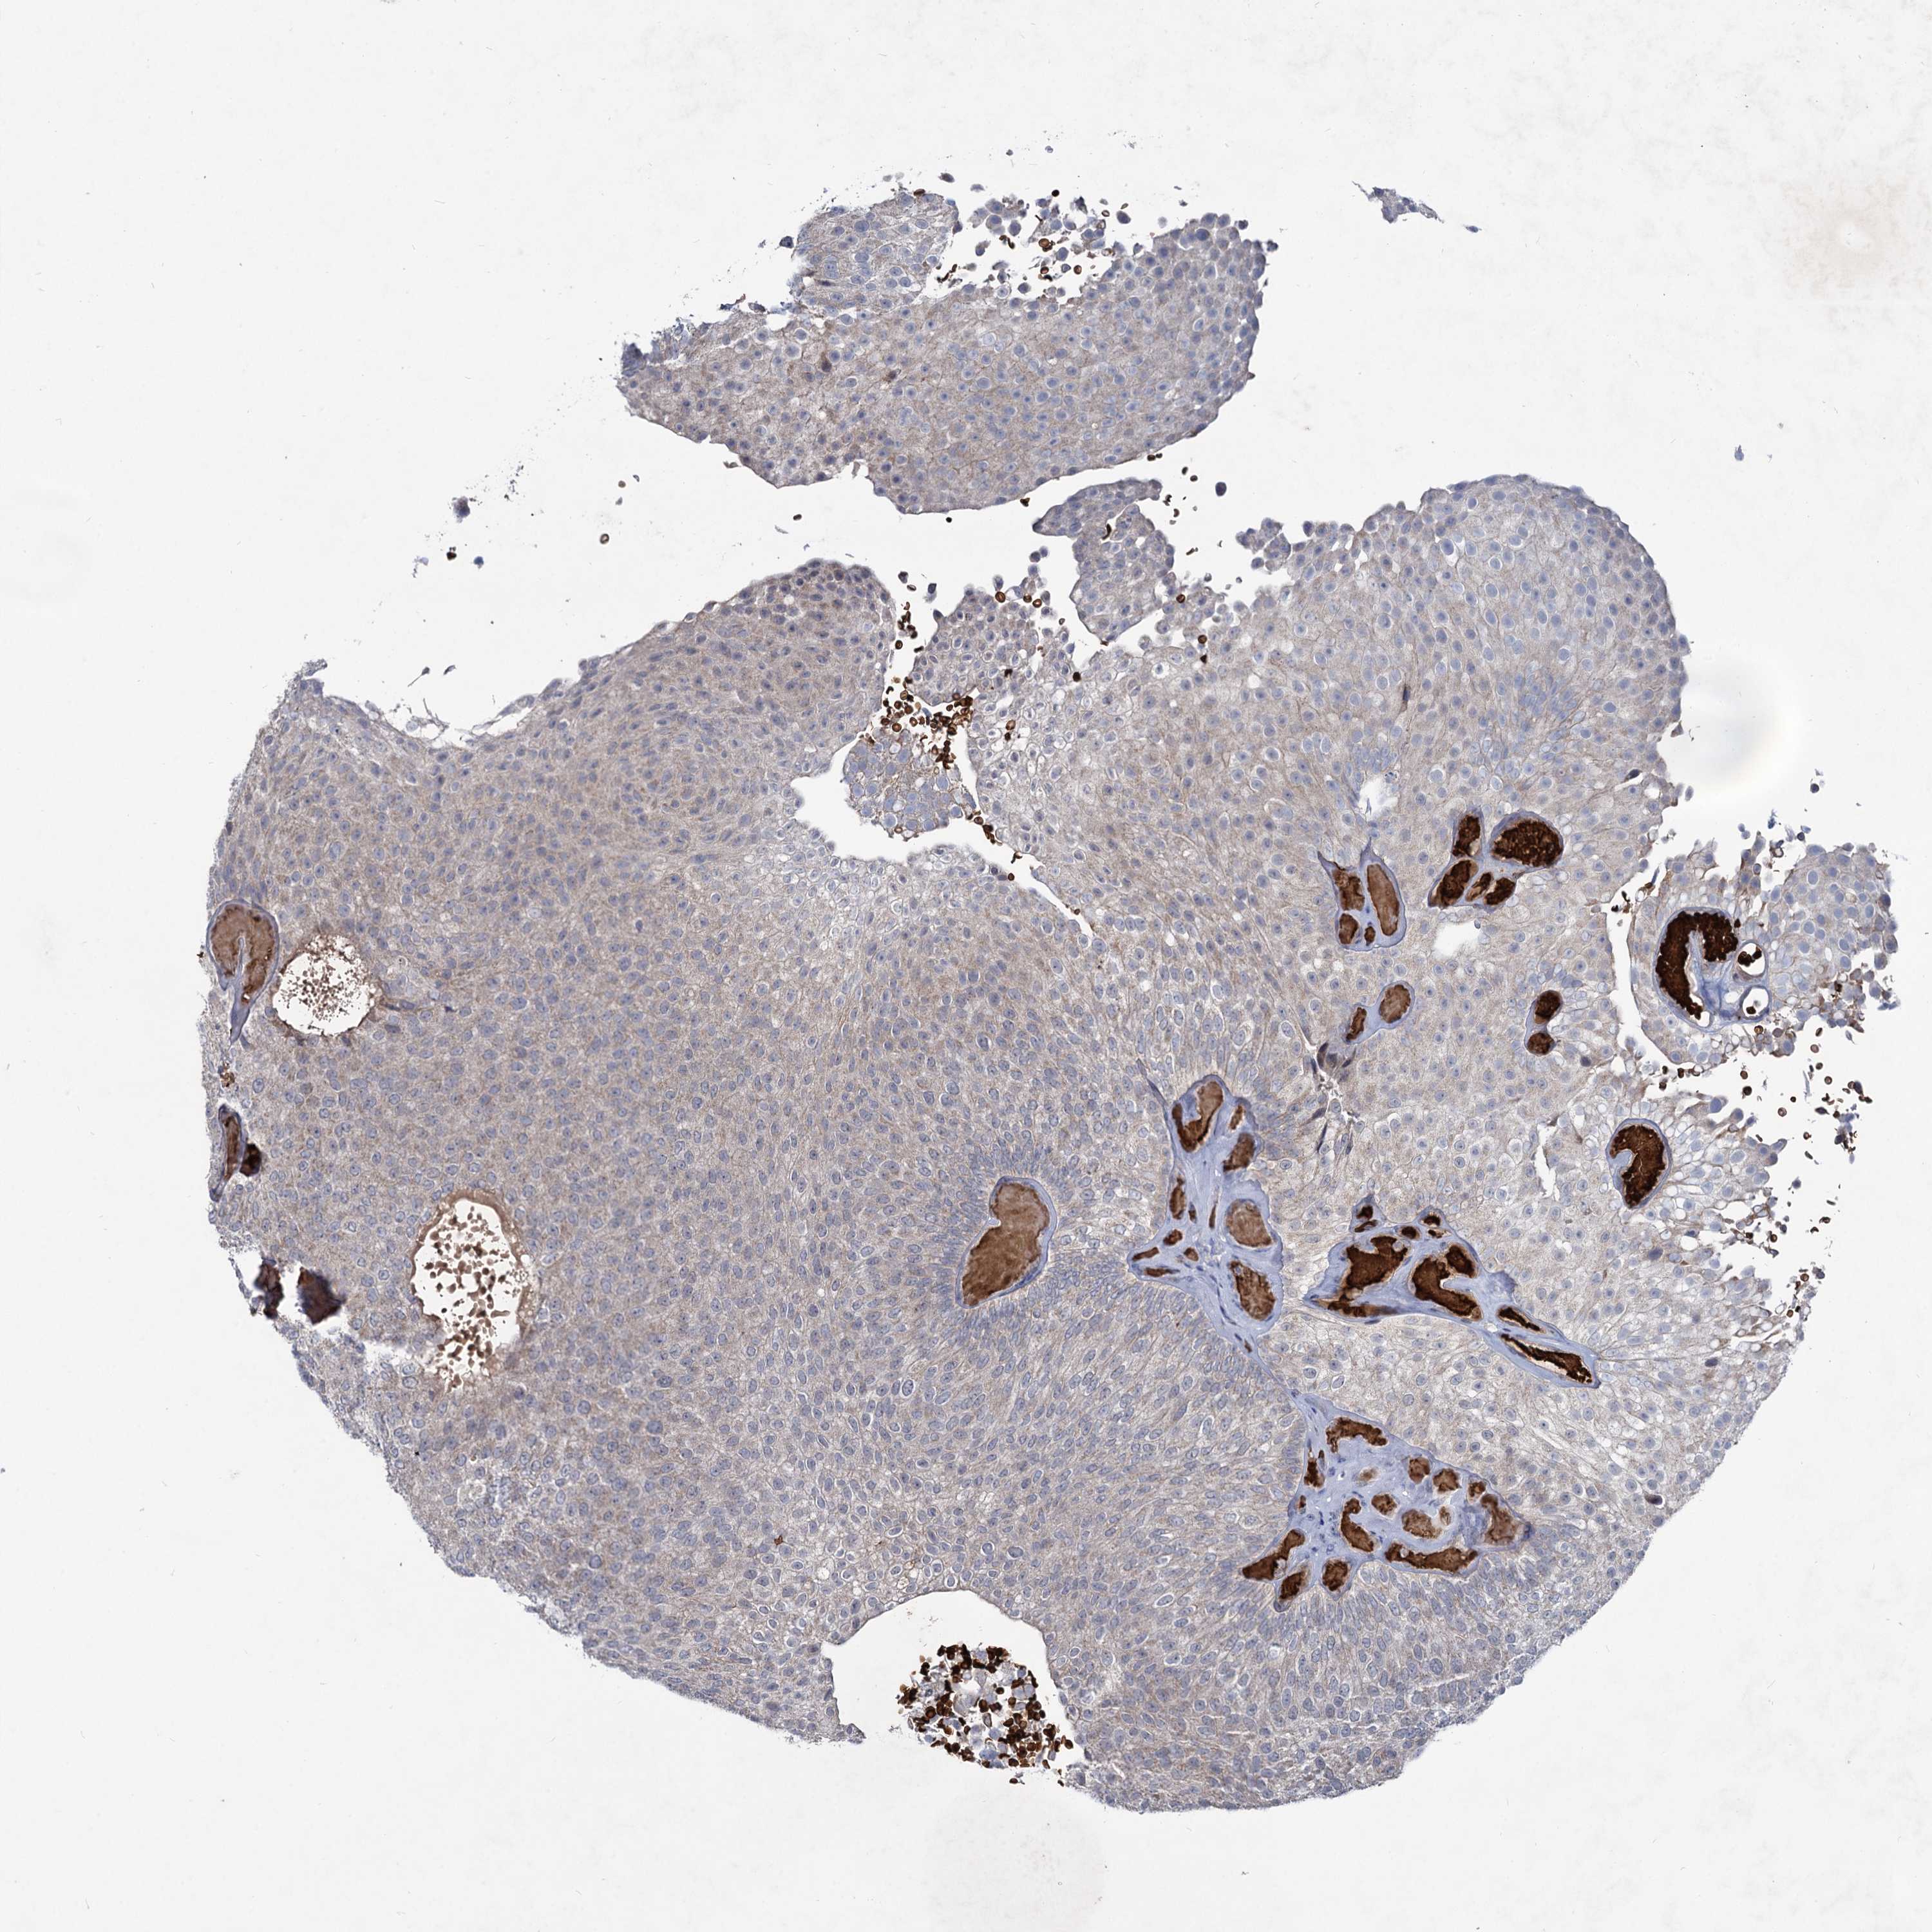

UROTHELIAL CANCER - Protein expressioni

A mouse-over function shows sample information and annotation data. Click on an image to view it in a full screen mode. Samples can be filtered based on level of antibody staining by selecting one or several of the following categories: high, medium, low and not detected. The assay and annotation is described here.

Note that samples used for immunohistochemistry by the Human Protein Atlas do not correspond to samples in the TCGA dataset.

Antibody stainingi

Antibody staining in the annotated cell types in the current human tissue is reported as not detected, low, medium, or high, based on conventional immunohistochemistry profiling in selected tissues. This score is based on the combination of the staining intensity and fraction of stained cells.

Each image is clickable and will lead to virtual microscopy that enables deeper exploration of all samples and also displays staining intensity scores, fraction scores and subcellular localization as well as patient and tissue information for each sample.

Antibody HPA039343

Antibody HPA040048

Urothelial carcinoma, High grade

Urothelial carcinoma, Low grade